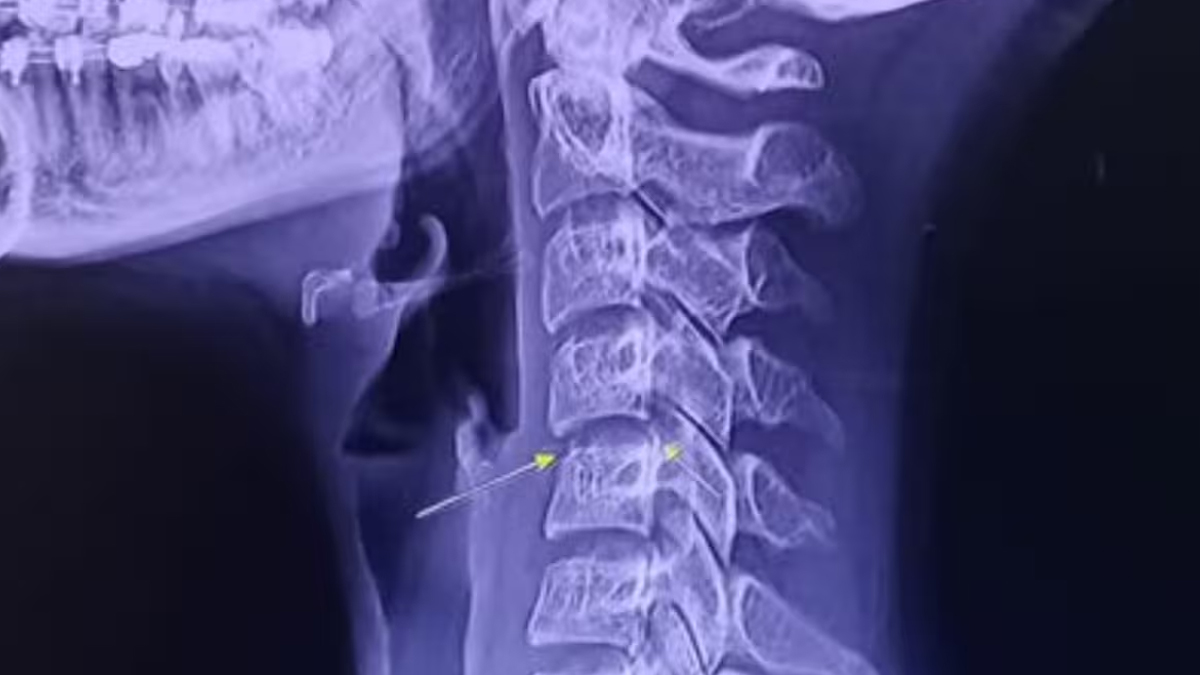

In her final social media posts, Chayada shared her worsening condition, accompanied by an X-ray of her spine. She urged her followers to be cautious when choosing massage therapies, warning of potential complications. Unfortunately, her health deteriorated further, and she was admitted to the ICU in Udon Thani. Medical reports later confirmed septicemia and brain swelling as the causes of her death, although an autopsy was required to establish a definitive link to the massage sessions.